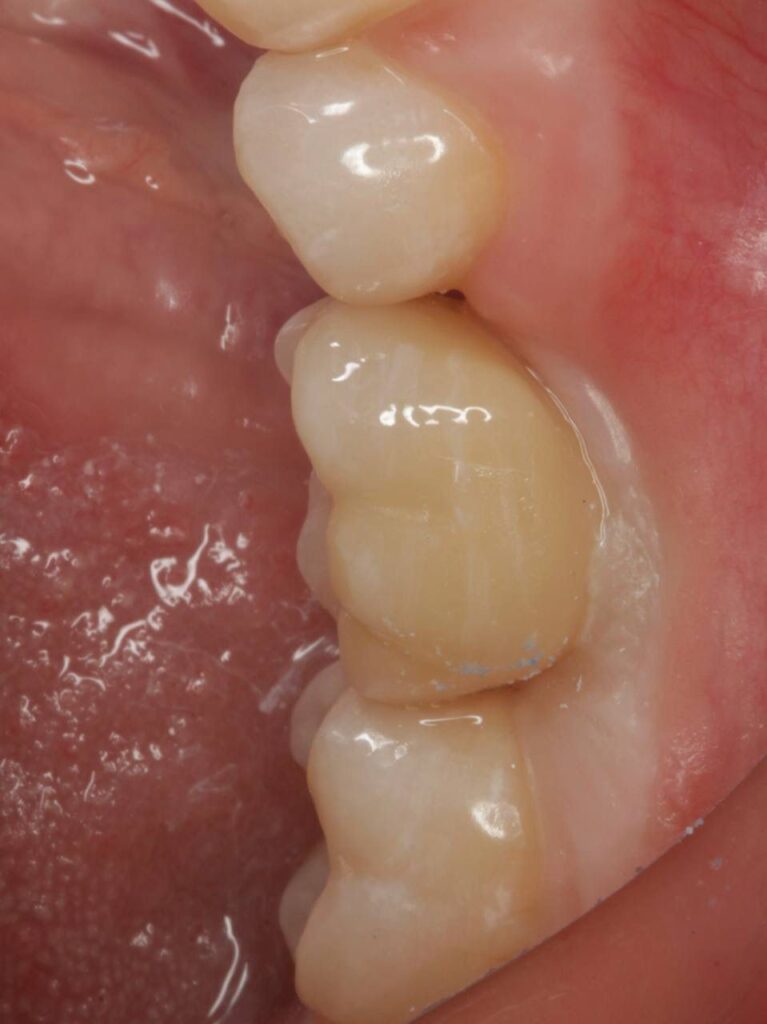

Специализация: терапия(эндодонтия), ортопедия, имплантология.